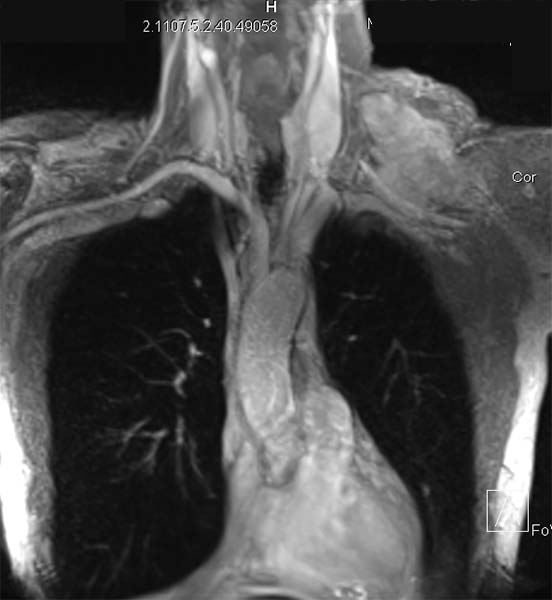

A 70-year-old male presented with a 16-month history of cervical and left shoulder pain. Computed tomography showed an oval solid lesion measuring 10 x 6 x 5.5 cm in the left lateral cervical space. An incisional biopsy revealed that the mass to be a low-grade spindle cell tumor compatible with DT. Magnetic resonance imaging of the neck and thorax showed an encapsulated lesion in the left lateral cervical region with marked contrast enhancement. The subclavian vessels and the brachial plexus were dislocated anteriorly, apparently not infiltrated by the mass (Figure 1).